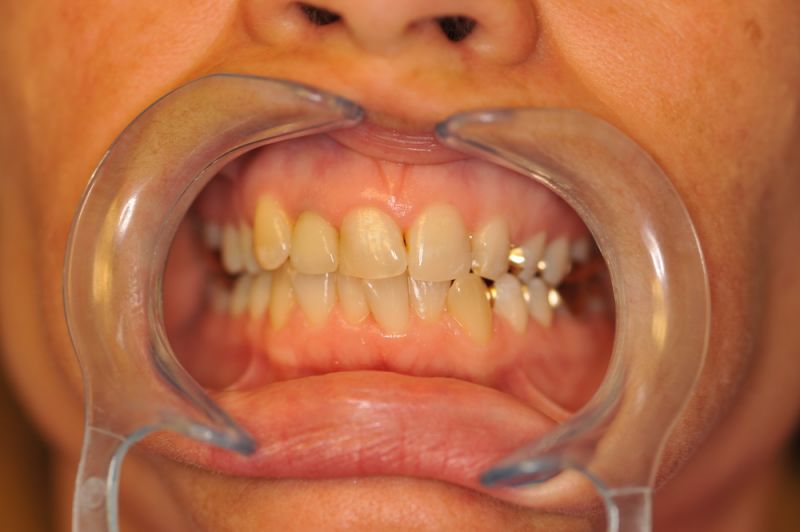

Patientin aus Uelzen zum Recall

11346

Wir würden gerne mal was Neues zeigen, es gibt nur nichts Neues.

Die Arbeit befindet sich seit 23 Jahren unverändert im Munde der Patientin!